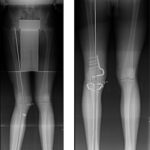

Dr. Mohan puttaswamy is a senior consultant and joint replacement surgeon at Fortis hospital, Bannerghatta road and Indian Orthopedic Research Institute (IORI clinic). With more than a thousand joint replacement surgeries to his credit in the last decade, he has a fantastic reputation in joint replacement speciality in India. He has done his fellowship training under Dr. Kenneth krackow one of the early inventors of total knee arthroplasty. With more than 10 international publications to his credit, Dr. Puttaswamy is a reviewer of the reputed journal of arthroplasty.

Dr. Puttaswamy graduated from Bangalore medical College in the year 2001 and then pursued his post graduation at Madras medical College, topping the University with two gold medals. He then moved to the United States pursuing fellowships in joint replacement surgery with Dr. Ken krackow and he is one of the few Indians who have trained in Harvard University with skills in deformity correction and pediatrics orthopedics. After two formal fellowship training from US, Dr. Puttaswamy has been associated with Fortis hospitals for more than ten years now taking care of complex orthopedic problems in joint replacement. The simple fact that patients from more than 15 countries across the world have sought Dr. Puttaswamy’s care is a testament to his expertise and credibility